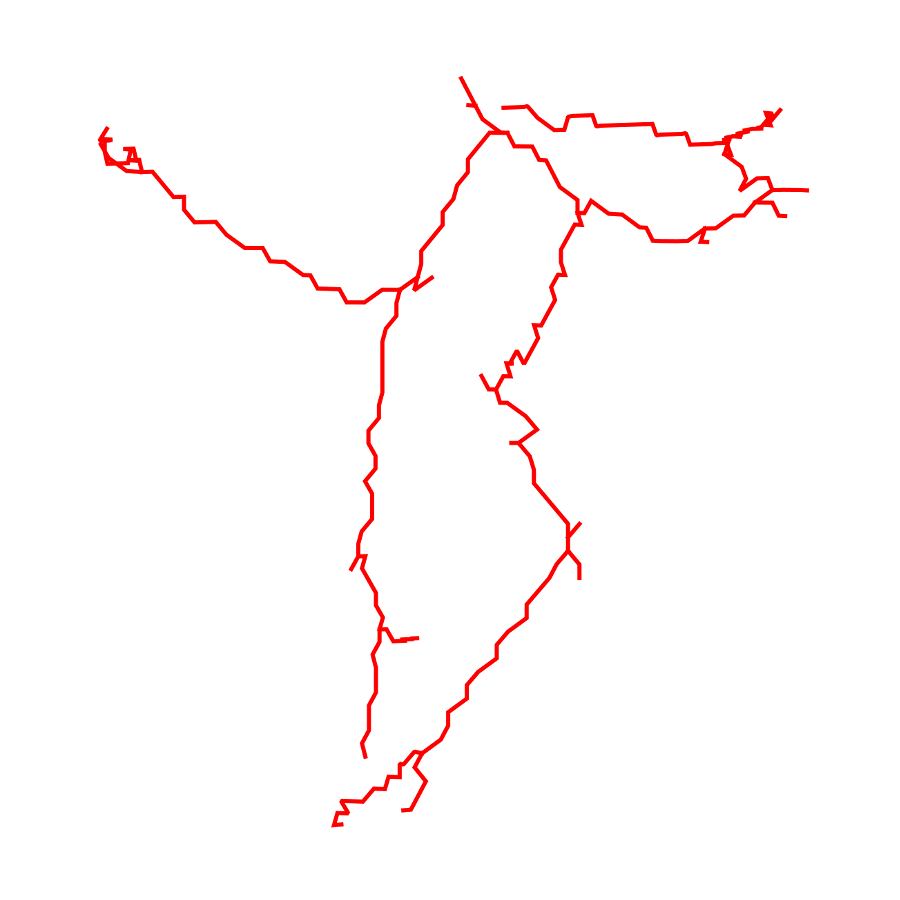

3.2 Connected Geodesic Paths as Vascular Tree

Representative examples of degraded synthetic images from SVT and the respective GT are shown in fig. 4 together with the connected graphs extracted by VTrails. Analogously, the same set of images are reported for the real images TOF and CTA in fig. 4. Qualitatively, the extracted set of connected geodesic paths shows remarkable matching with the provided GT in all cases. First, we verify the acyclic nature of the graph. We found no cycles, degenerate graphs and unconnected nodes, meaning that the extracted connected geodesic paths represent a connected geodesic tree. Precision and recall are then evaluated for the identified branches. Also, error distances are determined as the connected tree’s binary distance map evaluated at GT. Average errors () precision and recall are reported (meanSD) in table 1. Note that no pruning of any spurious branches is performed in the analysis.